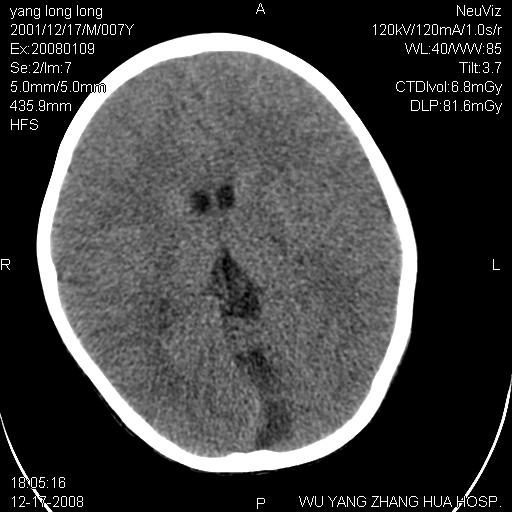

标题: PED1686:M7Y,头外伤,家人及自诉平时无任何不适。 [打印本页]

标题: PED1686:M7Y,头外伤,家人及自诉平时无任何不适。

考虑蛛网膜囊肿,请老师们看看多指导指导。

多考虑大枕大池。本例颅骨歪歪的,灶后枕骨似有膨胀征像(为蛛网膜囊肿征像),但整个左侧枕叶后方枕骨均有向后膨隆,所以暂不考虑蛛网膜囊肿。必要时随访

鉴别巨大枕大池与蛛网膜囊肿之间,倾向前者。

枕大池蛛网膜囊肿

蛛网膜囊肿可能性大

考虑枕大池蛛网膜囊肿

考虑枕大池蛛网膜囊肿。建议必要时mri检查。

病变向两侧延伸,颅骨内板受压侵蚀,似有张力!!还是考虑蛛网膜囊肿!!